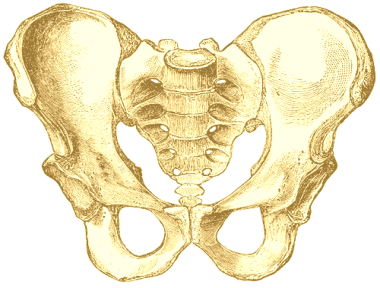

Você sabe onde fica a articulação sacroilíaca? Sabia que ela pode ser a fonte de uma dor crônica na coluna lombar e nas nádegas?

As articulações sacroilíacas (SI) podem ser responsáveis pela etiologia (causa) de até 30% das dores lombares. A dor originada nestas articulações, que unem a porção final da coluna vertebral (sacro) ao quadril (ilíaco) bilateralmente, pode ser referida para a região lomb ar, nádegas, virilha e membros inferiores.

ar, nádegas, virilha e membros inferiores.